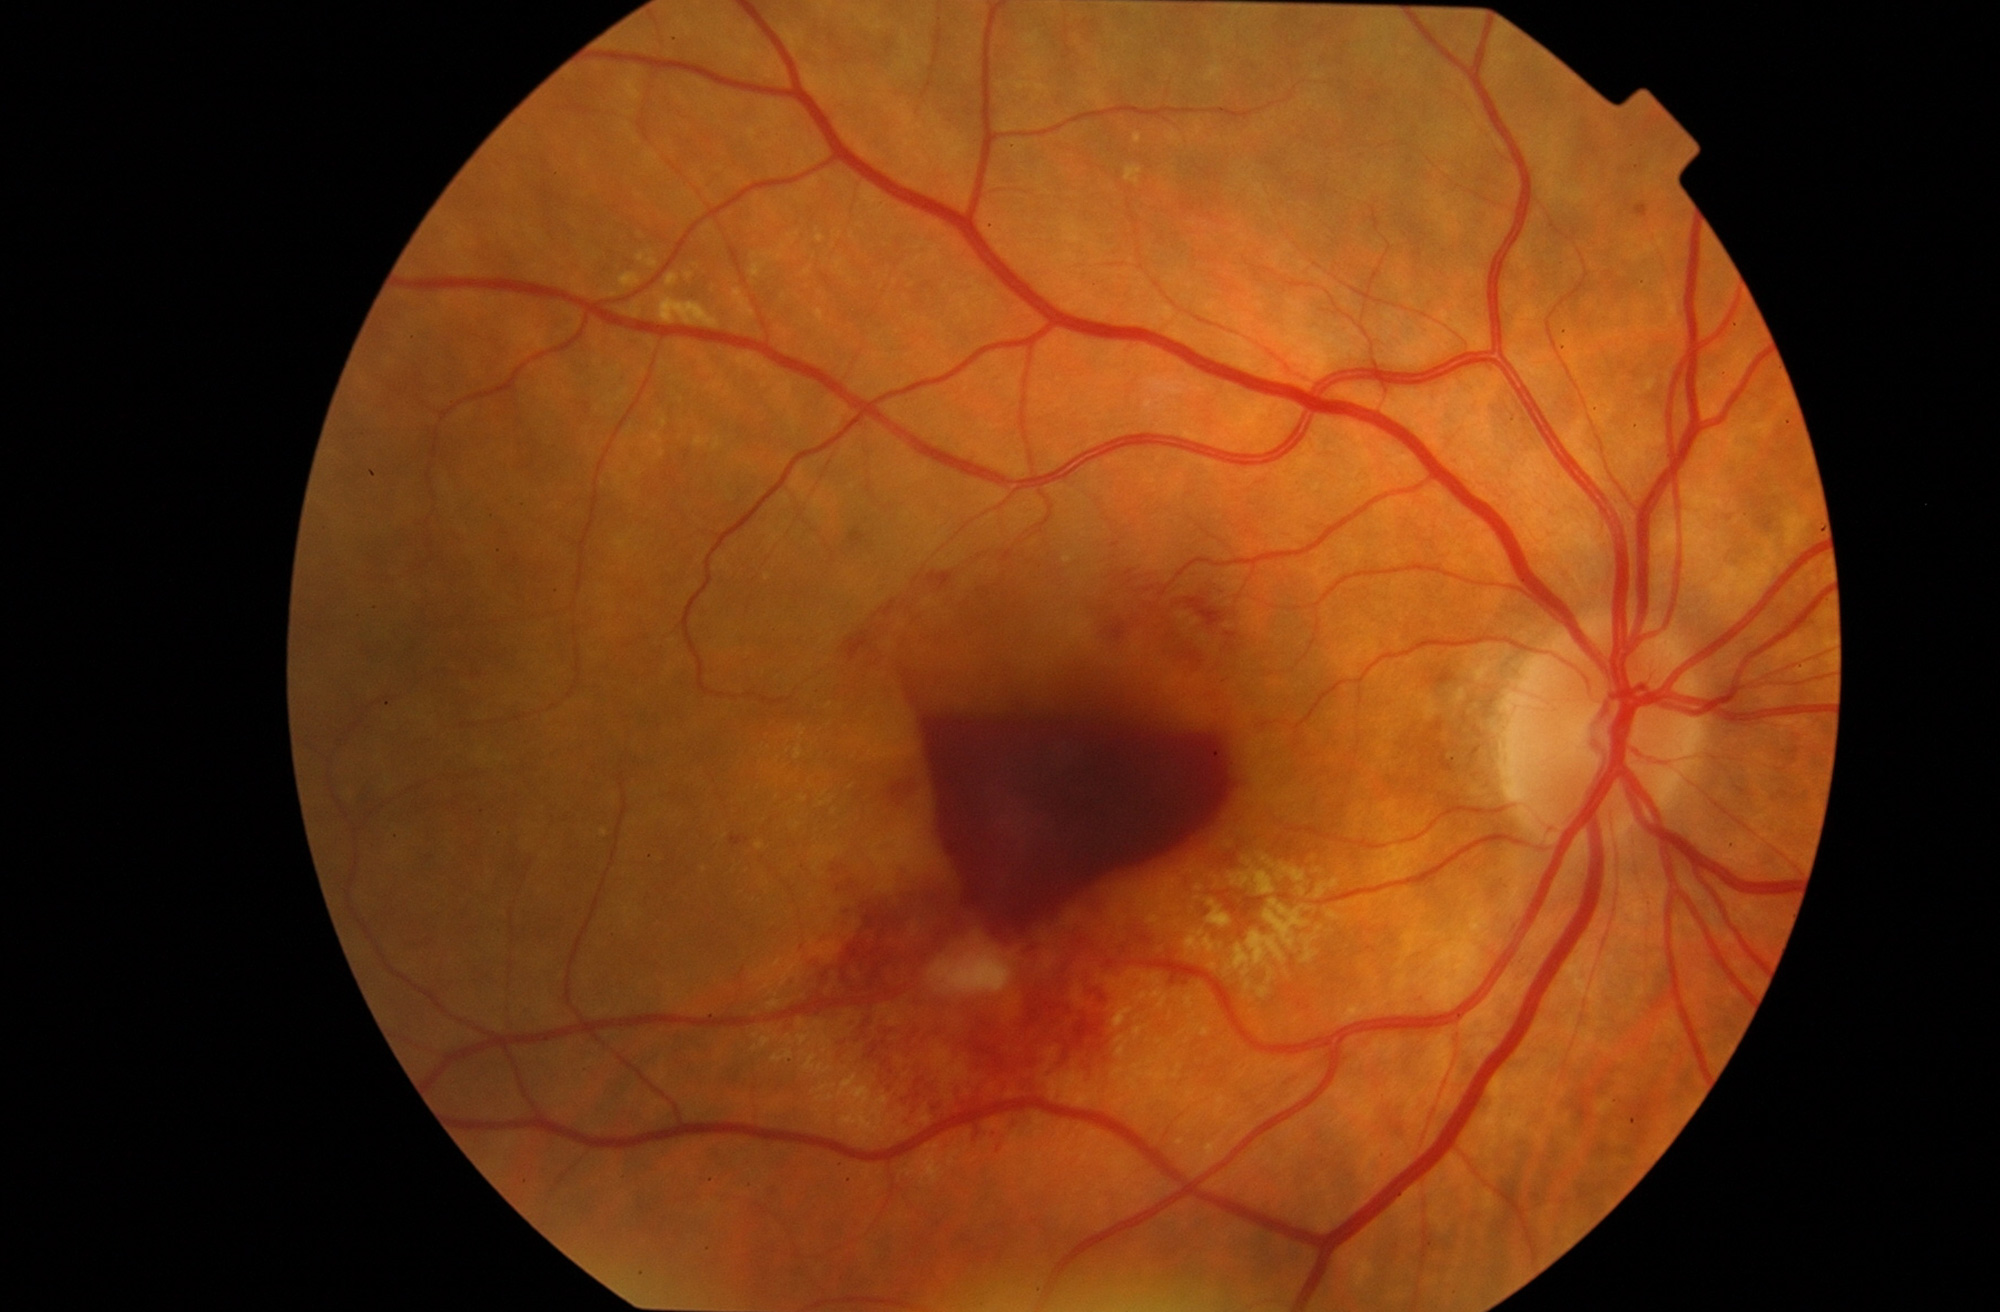

Hemorragia intraocular

Son varias las enfermedades que pueden dar un sangrado intraocular. Las más frecuentes son la retinopatía diabética, el desgarro retiniano, la degeneración macular asociada a la edad o un traumatismo ocular.